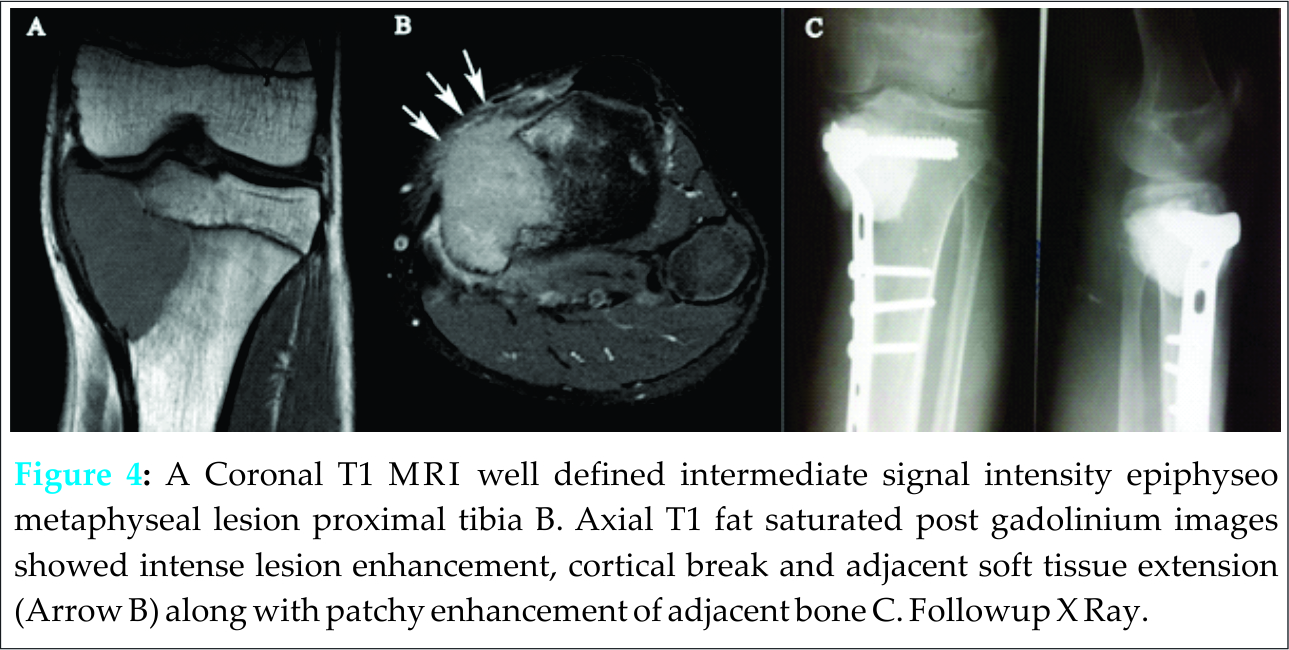

Case Report: A fifteen year old child presented to department of orthopedics of our institute with complaint of difficulty in moving upper limb and swelling distal humerus. Another patient who was a 13 years old male had painful ambulation and swelling in upper tibia. MRI followed by core needle biopsy was done in both the patients confirming the mass to be giant cell tumor which is quite rare in this age group. First patient was managed by wide excision and total elbow replacement and second one by curettage, cementation and augmentation with plate-screw construct.

In our orthopaedic oncology clinic we have come across two pediatric patients having giant cell tumor of bone in last two years. First patient was a 15 years old male child presenting to us with history of pain, swelling in right distal humerus for last three months. Second patient was thirteen years old male who came with a history of swelling proximal tibia and painful ambulation for last four months. Their detailed clinicopathological profile is given in Table 1. There was no antecedent history of trauma or systemic disease. Radiologically features of epiphyseometaphyseal lesion, thinned out cortices, physeal destruction and wide zone of transition were noted more so in first patient. Keeping in view age of patients and radiological appearance differential diagnosis- of chondroblastoma, brown tumor, aneurysmal bone cyst and giant cell tumor were kept. Biochemical profile revealed normal serum alkaline phosphatase levels thereby excluding hyperparathyroidism. MRI in both patients was suggestive of GCT which was confirmed by histopathology examination.

Case 2 had minimal cortical breach and a small soft tissue component. Hence this patient was managed by extended curettage, cementation and plate-screw construct augmentation. There was wound dehiscence at six weeks in this patient which was managed by gasrtrocnemius flap [Fig.3]. Both the patients are free of recurrence at one year follow up.